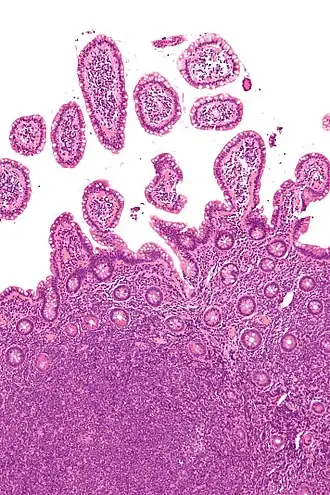

![]() Микрофотография мантийноклеточной лимфомы, одной из разновидностей неходжкинской лимфомы. Дистальный отдел подвздошной кишки. Окраска гематоксилин-эозином. | |